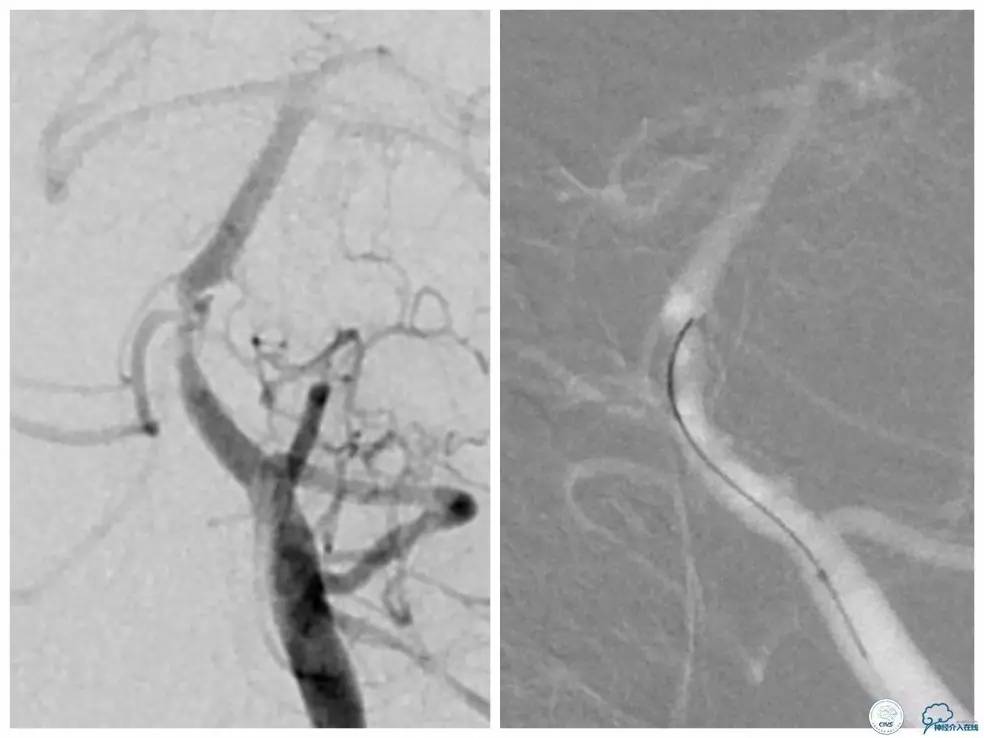

全麻下,右股动脉入路, 6F导引导管放至右椎动脉V2段远端,Transend微导丝(0.014″300cm)+Echelon-10微导管至基底动脉狭窄段近端,反复多次尝试不能通过狭窄段(图7)。

图7

遂换用Traxcess微导丝(0.014″200cm)+Echelon-10微导管越过狭窄段后,重新交换Transend微导丝至右大脑后动脉P2段,Gateway球囊(2.0mm×9mm)扩张后,放置Apollo支架(2.5 mm×13mm)至狭窄段,球扩释放后支架贴壁良好,残余狭窄约15%,前向血流TICI3级(图8)。

图8